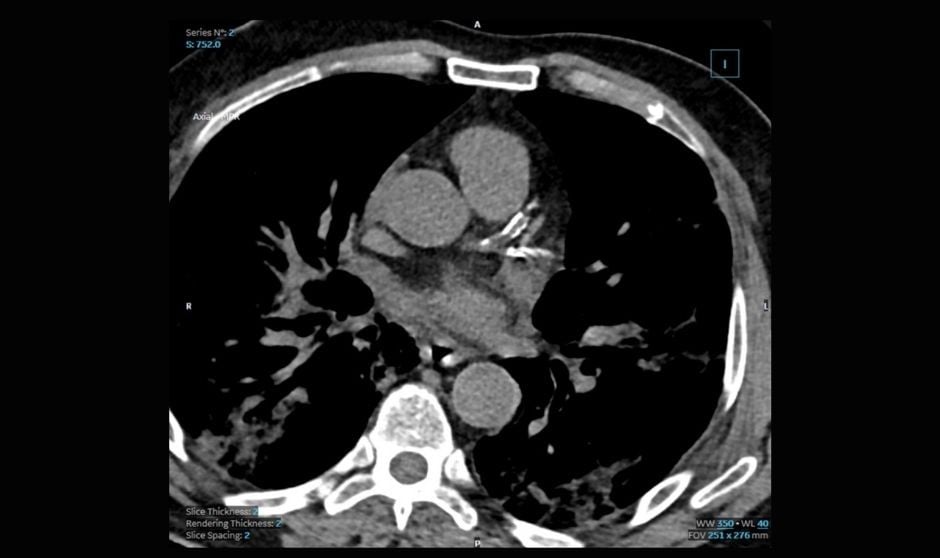

Anotaciones de imagen por tomografía computarizada.

Una investigación realizada en 20 hospitales universitarios franceses ha evidenciado que la tomografía computarizada es el mejor predictor de mal pronóstico Covid-19. Este proceso de obtención de imagen permitió un diagnóstico correcto de la neumonía causada por el SARS-Cov-2 durante la primera ola de la pandemia del coronavirus en Francia.

El estudio contó con una muestra de cohorte retrospectivo de 10.735 sujetos sospechosos con neumonía causada por el coronavirus. La investigación arrojó que la precisión diagnóstica de la tomografía computarizada general fue del 80 por ciento, considerando la RT-PCR como estándar de referencia, y aumentó al 86,3 por ciento después de 5 días de síntomas.

El modelo de riesgo de resultado grave mejoró cuando las variables clínicas se combinaron con anotaciones de tomografía computarizada, siendo la extensión del daño parenquimatoso pulmonar el predictor más fuerte.